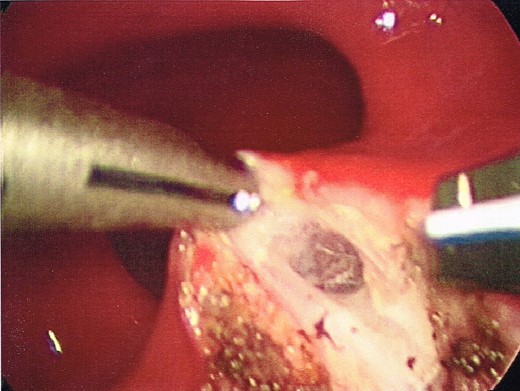

Once the dissection plane was entered, insufflation of the perirectal extraperitoneal space allowed for excellent exposure for a combination of blunt and Harmonic Scalpel dissection (Figs 4 and 5).

The dome of the cyst is visible at the bottom of the image (indicated by arrow), with a dissection plane visualized above.